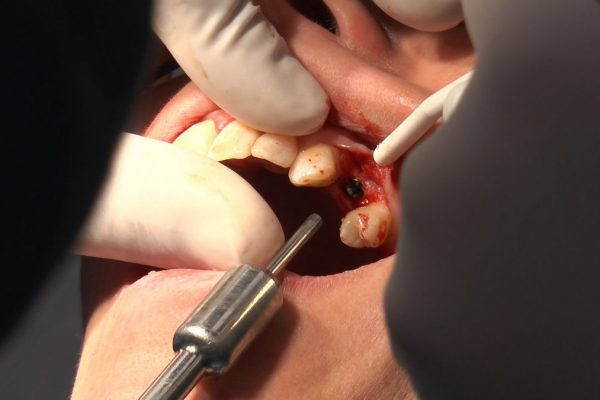

W ostatni weekend czerwca 2018 roku kursanci II Sezonu Preludium Implantologii odbyli piątą, finałową sesję, która w całości podporządkowana była praktyce. W ciągu dwóch dni zabiegowych Lekarze uczestniczący w szkoleniu przeprowadzili szereg zabiegów pod kierunkiem dr n.med. Violetty Szycik. Wszczepili 17 implantów oraz przeprowadzili ekstrakcje i zabiegi regeneracyjne kości. Zabiegi były wykonywane także w sedacji dożylnej z udziałem specjalisty anestezjologii i intensywnej terapii dr Jolanty Grzybowskiej. Preludium implantologii to nowy program edukacyjny dla adeptów implantologii stomatologicznej, którego celem jest wprowadzenie do implantologii poprzez pozyskanie wiedzy w szerokim zakresie i uwzględnieniem szczegółów mających decydujące znaczenie dla powodzenia leczenia implantologicznego. Ale tak jak wszystkie szkolenia w Instytucie Vivadental, w tym wiodące Practiculum Implantologii, zorientowane jest na praktyce i samodzielnym wykonywaniu zabiegów pod kierunkiem Mentora. To najlepsza edukacja w medycynie zabiegowej, a zarazem najlepszy start do implantologii.